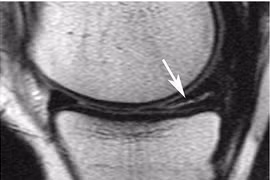

(khoahocdoisong.vn) - Bị rách sừng sau sụn chêm trong và ngoài gối trái thường để lại dấu hiệu hơi ê đùi gối, khi đi xuống cầu thang thì phát ra tiếng kêu to như bẻ ngón tay. Trường hợp này có thể phải chỉ định phẫu thuật nội soi xử trí tổn thương.

(khoahocdoisong.vn) - Sụn chêm có vai trò quan trọng trong hoạt động chức năng của khớp gối. Sụn chêm lại rất dễ bị tổn thương trong các chấn thương khớp gối và là một trong những nguyên nhân quan trọng gây thoái hóa khớp gối.